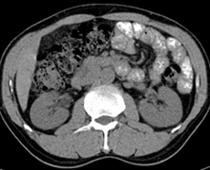

患者,男,57,常年不吃午饭,近一个月来腹部隐痛,无明显黄疸,明天进行增强扫描,图象另上传,麻烦各位帮忙一起看看讨论讨论

肝外胆管扩张,胰头增大,肠系膜上静脉似有包埋征象。

考虑:胰头占位性病变,建议增强进一步检查。

肝内外胆管扩张,胆管未端阻塞,建议mri检查

考虑肝总管或胆总管占位性病变,建议mrcp或ercp.

胰头增大,胆总管增宽,考虑胰头癌可能性大,明天看增强片有助诊断.